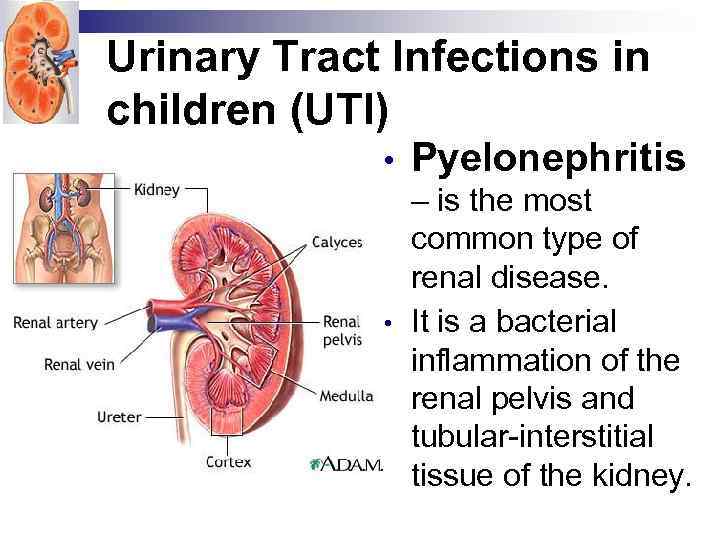

Urinary Tract Infections in children (UTI) • • Pyelonephritis – is the most common type of renal disease. It is a bacterial inflammation of the renal pelvis and tubular-interstitial tissue of the kidney.

Urinary Tract Infections in children (UTI) • • Pyelonephritis – is the most common type of renal disease. It is a bacterial inflammation of the renal pelvis and tubular-interstitial tissue of the kidney.